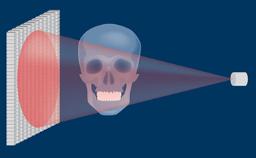

Structured Assessment and Treatment Planning

Introduction to Radiographic Assessment

Learning Module